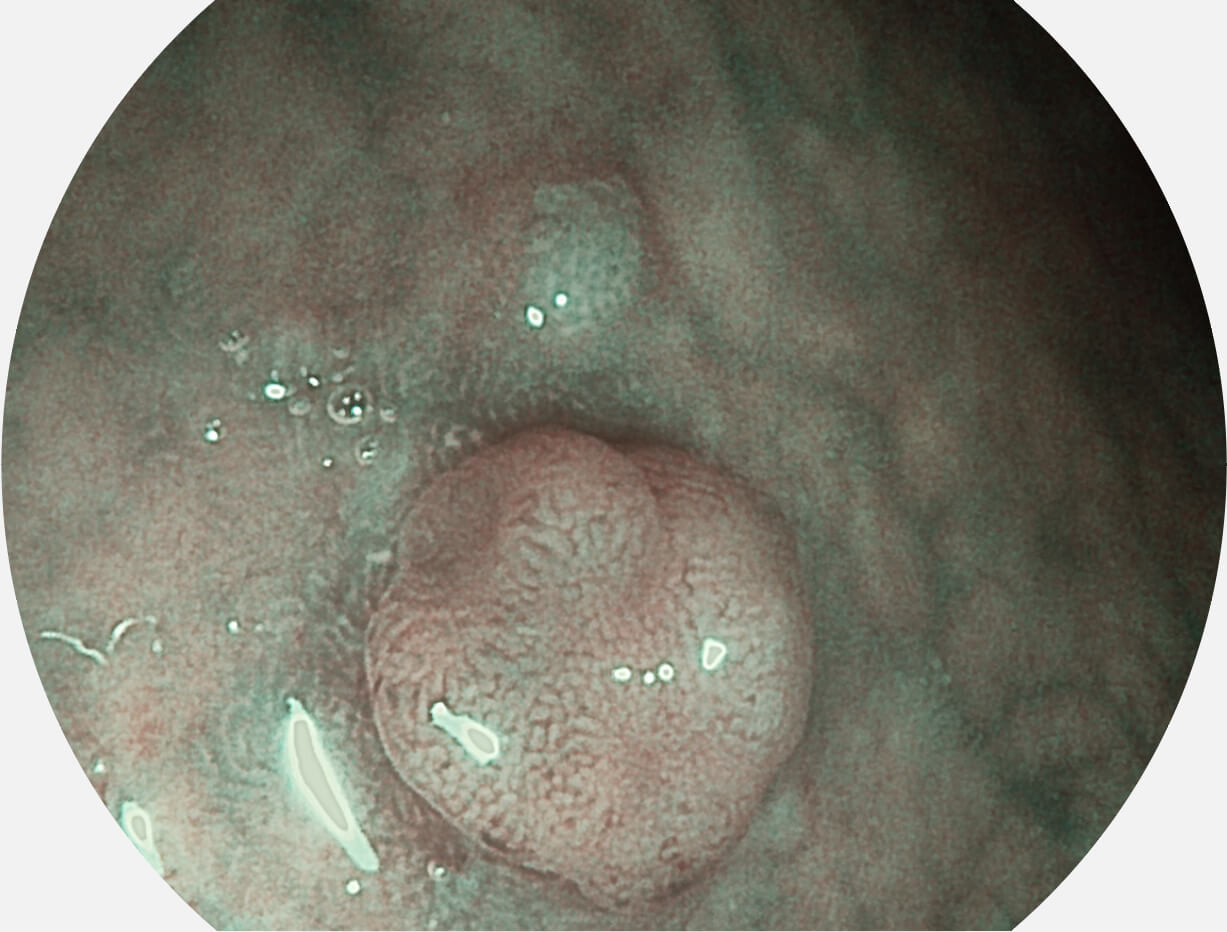

SFI图像

白光图像

图像具有高亮度、高黏膜血管颜色对比度的特点,且不改变粘液、食物残渣、粪便的基本颜色,可在中远景下进行观察,助力消化道早期疾病的诊断。